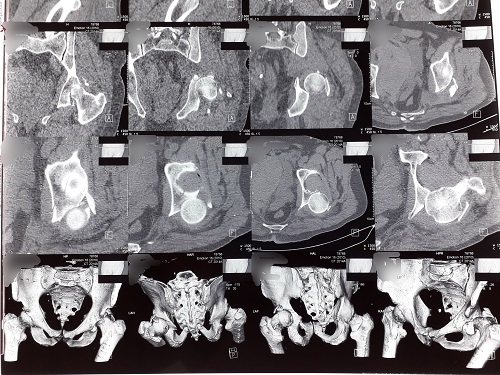

В заклад поступив пацієнт похилого віку після тривалого лікування, терміном понад 1 місяць, зі складним переломом кісток тазу та вивихом голівки стегнової кістки. В комплекс стандартних діагностичних заходів було включено новітній – на основі методу 3D моделювання та друку. На просторовому принтері було створено полімерну модель ділянки травматичної деструкції, що дозволило хірургам ортопедам-травматологам розробити тактику оперативного втручання з максимальною точністю та планування ходу та об’єму оперативного втручання. Це стало можливе завдяки активній співпраці співробітників кафедри терапії та сімейної медицини (доц. Михалко Я.О. – моделювання та 3D друк), хірургічних дисциплін (доц. Василинець М.М. – планування та проведення операції) факультету післядипломної освіти та доуніверситетської підготовки та кафедри загальної хірургії (доц. Шерегій А.А. – передопераційна підготовка та проведення операції) медичного факультету.

За словами завідуючого відділення травматології та ортопедії та доцента кафедри хірургічних дисциплін ФПОДП ДВНЗ «УжНУ» Василинця М.М., застосування революційних технологій 3D друку є актуальним напрямом сучасної травматології. В багатьох наукових роботах було показано, що використання друкованих 3D моделей під час передопераційного планування потенційно дозволяє скоротити час самого втручання, підібрати відповідні до індивідуальних потреб найбільш оптимальні імпланти та зменшити об’єм крововтрати. Разом з тим, наочна візуалізація зони ураження на моделі дозволяє довести до свідомості пацієнтів важкість стану та особливості хірургічного втручання, підвищує розуміння хворим самої процедури та збільшує його прихильність до лікування, що відповідає пацієнт-орієнтованому підходу в сучасній медицині. Не менш важливим є також той факт, що отримані моделі можуть слугувати в якості наглядних посібників при підготовці лікарів-інтернів, клінічних ординаторів.